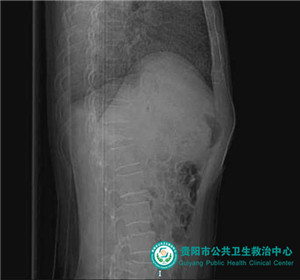

術(shù)前椎體前緣陳舊性缺損、壓縮